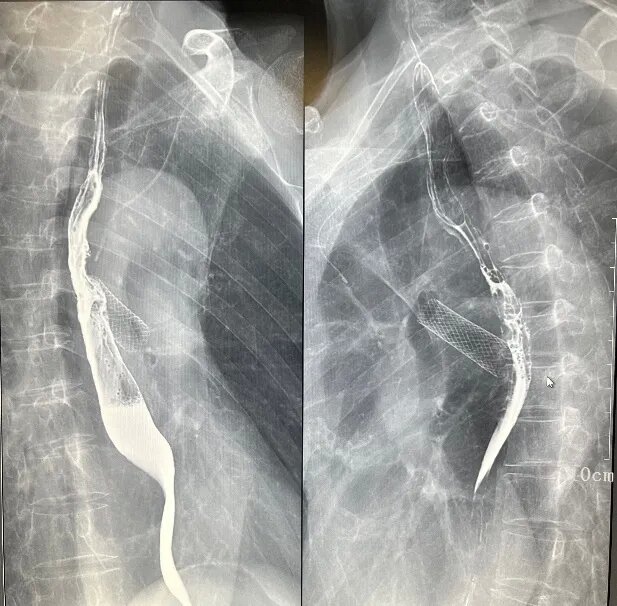

三、介入診療

如膽道造影、T管造影、ERCP,支持簡單的介入治療。